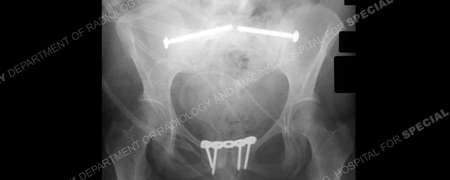

Diagnostic work-up included standard radiographs of the pelvis demonstrating widening of the symphysis pubis of 9 cm and opening of both sacroiliac (SI) joints posteriorly. A CT scan using 2 mm thin cut technique was performed to evaluate the posterior pelvic ring and SI joints. The CT scan demonstrated bilateral sacroiliac joint disruptions. In addition, a MRI scan documented disruption of the pelvic floor and extensive hematoma. Imaging studies revealed an unstable pelvic dislocation with significant symphyseal widening and disruption of the posterior pelvis equivalent to an APC III, or Tile Type C pelvic injury. Open reduction and internal fixation (ORIF) of the pubic symphysis was performed with placement of a contoured 5-hole 3.5 mm pelvic reconstruction plate and screws. Anatomic reduction and stabilization of SI joints were performed using bilateral posterior ilio-sacral screw arthrodesis. Under fluoroscopic control bilateral single 7.3 mm cannulated screws were inserted percutaneously into the body of S1. The perioperative course was unremarkable. She followed up at regular intervals and reported progressive resolution of pain symptoms. The SI screws were removed at 2 years due to mild radiographic evidence of screw loosening. She returned at 2.5 months following hardware removal and reported complete pelvic pain relief and return to pre-injury activities.

Immediate post-operative radiographic anteroposterior x-ray demonstrating an anatomic reduction of symphysis pubis and symphysiodesis using anterior plating. SI joint reduction and arthrodesis using 7.3 mm cannulated screws have been performed bilaterally.